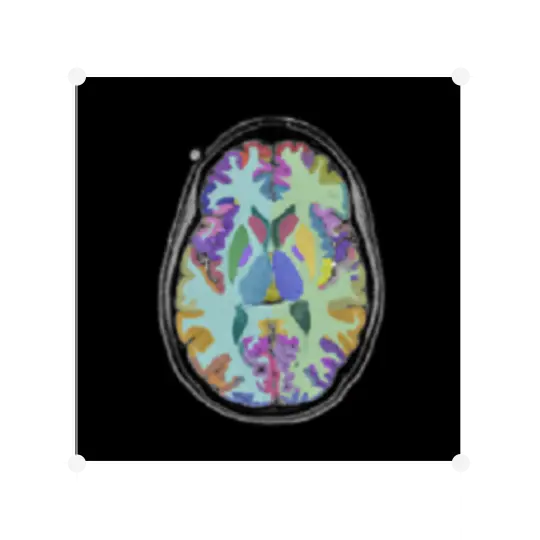

Changes in brain volume, or atrophy, are among the most established effects of many neurodegenerative diseases. IXICO have been providing volumetric analysis for late-phase trials for our partners for more than 12 years, measuring brain volume both cross-sectionally and longitudinally using our LEAP (Learning Embeddings for Atlas Propagation) pipeline, which provides the following measures:

• Global – making measurements on the whole brain

• Regional – measuring specific local brain regions

IXICO also cover a range of volumetric solutions, including Freesurfer, MIDAS BSI and synthSEG.

IXICO's proprietary deep-learning platform, IXI™ can provide highly accurate automated segmentations of the caudate, putamen, thalamus, whole brain and lateral ventricles. For the caudate, whole brain and ventricles, the IXI™ Platform’s segmentations are then combined with an updated version of the Boundary Shift Integral (BSI) algorithm, the generalised BSI (gBSI; Prados et al. 2015).

Since IXI™ was released, IXICO have used the gBSI pipeline in a number of our clinical trials, and it has also been used for the volumetric analyses of the HD-IH consortium study. gBSI is a modern solution for the original MIDAS-BSI with comparable sensitivity but more efficient and cost-effective to run.

In addition to volumetric endpoints, IXICO also provide cortical thickness measures from Freesurfer.